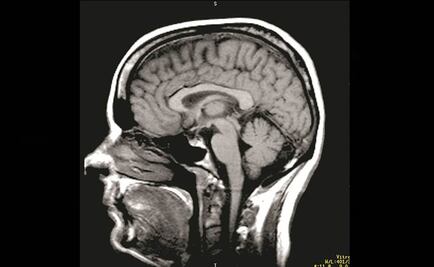

Procesa diariamente unos 60 mil pensamientos